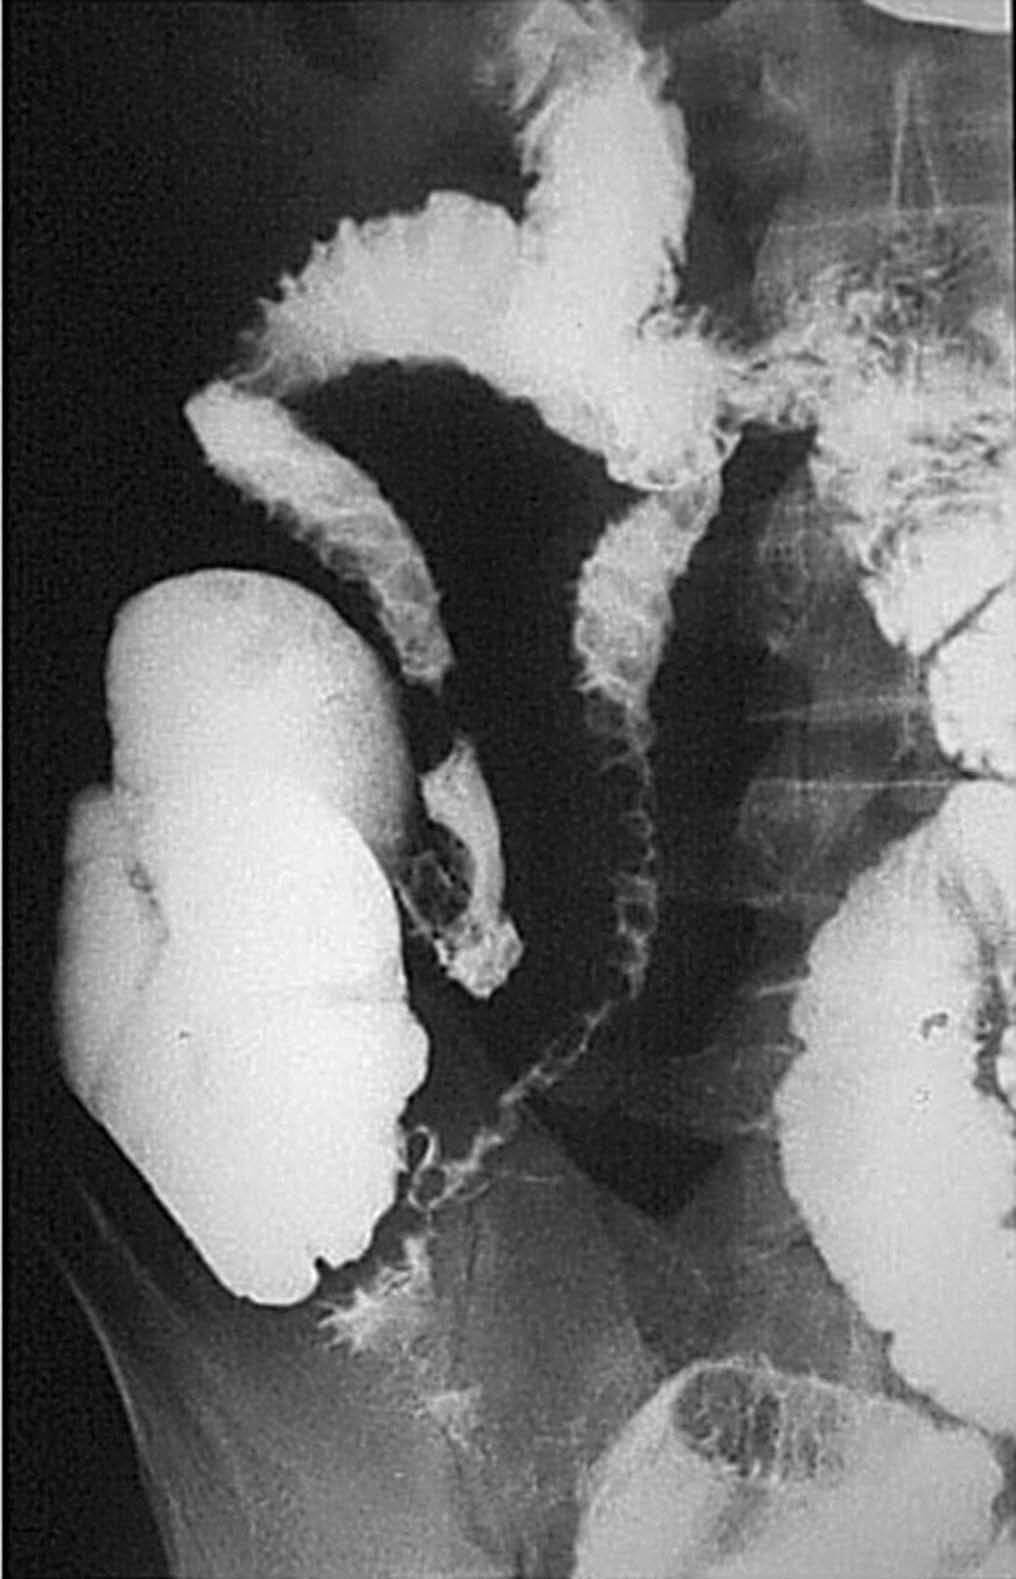

En la fase activa hay presencia de úlceras superficiales o aftoides (fig. 4). Pueden evolucionar haciéndose ulceraciones fisurantes longitudinales y transversales, dejando entre sí islotes de mucosa normal, constituyendo el concepto de patrón en "empedrado" (fig. 5).

Fig. 4.--Enfermedad de Crohn, fase activa inflamatoria. (A) En el estudio baritado, a nivel de íleon distal se observan pequeñas imágenes puntiformes de cúmulo de bario rodeadas de un halo de edema, que corresponden a úlceras superficiales o aftoides. (B) Correlación endoscópica.

Fig. 5.--Enfermedad de Crohn, fase activa inflamatoria. (A) Ulceraciones longitudinales y transversales que dejan entre sí islotes de mucosa edematosa, constituyendo el patrón en "empedrado" en el estudio baritado. (B) Correlación microscópica: ulceración fisurante rodeada del infiltrado inflamatorio, lesión claramente delimitada y rodeada de mucosa normal.

Al nivel de íleon terminal el espasmo justifica el signo de "la cuerda" (fig. 6). En relación no sólo con el espasmo, sino con una proliferación fibroadiposa del mesenterio aparece el signo del "asa orgullosa" en el estudio con bario, cuyo sustrato fisiopatológico ilustra la TC (fig. 7).